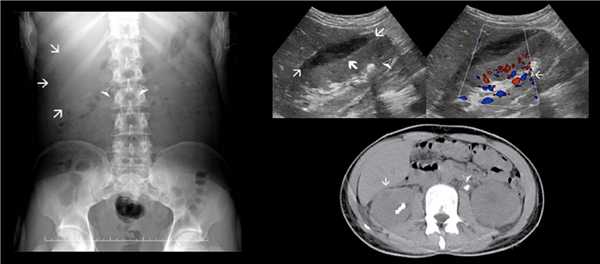

Рисунок. Пациент с жалобами на дискомфорт при мочеиспускании. На УЗИ правая почка расположена в малом тазу, сосудистый пучок от подвздошных сосудов (1); в лоханке гиперэхогенное включение с акустической тенью позади, размер 10х10 мм (3, 4). Заключение: Тазовая дистопия правой почки. Эхо-признаки конкремент в лоханке справа. На рентгене (4) по средней линии над S1 позвонком округлое рентгенконтрастное включение.

Рисунок. Пациент с мочекаменной болезнью поступил с острой болью в пояснице слева. На рентгене (1) границы правой почки увеличены, рентгеноконтрастные камни в обеих почках (треугольники). На УЗИ (2, 3) в правой почке чечевицевидное аваскулярное гипоэхогенное образование с неоднородной эхоструктурой сдавливает паренхиму; в зоне ЧЛК гиперэхогенный очаг с дорзальной тенью (треугольник), при ЦДК артефакт мерцания. Заключение: Субкапсулярная гематома правой почки. Конкремент в ЧЛК справа, без признаков обструкции. На КТ в правой почке субкапсулярная гематома и конкремент в лоханке; в левой почке конкремент в мочеточнике и вторичный гидронефроз 2-3 степени.